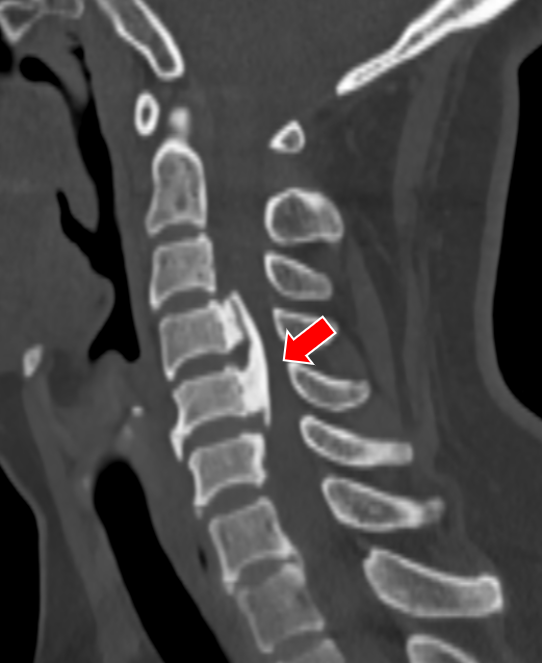

无独有偶,我院骨科还为一对姐弟完成了一组颈椎后路手术。姐弟俩吕艳、吕飞(化名)均患有“颈椎后纵韧带骨化症”。弟弟吕飞今年40岁,是位企业白领。别看他年龄不大,其实已多年饱受颈椎病之苦。由于长期伏案工作,这些年他常常感觉自己四肢乏力,走路像踩在棉花上一般,像系纽扣、写字这样的活动也逐渐无法完成,这让他很是着急。通过亲友介绍,他找到姜为民主任寻求帮助,姜主任在仔细的查体和阅片后,判断吕飞的颈椎后纵韧带骨化节段多,症状重,应当尽早手术,解除对脊髓的压迫。

(颈椎CT提示患者C3-6椎体后纵韧带骨化明显,椎管狭窄显著)

就在吕飞出院的当天,另一位症状相似的脊髓型颈椎病患者吕艳也来办理了住院手续。原来她是吕飞的亲姐姐,今年46岁。姐弟俩的症状和影像学表现都几乎相同,可见颈椎后纵韧带骨化确有一定的家族遗传倾向。吕艳告诉我们,他们姐弟这些年看过不少医生,都建议尽早手术,但因为听说颈椎手术风险极高,所以一直都选择“拖字诀”处理。这次吕飞的手术效果,给了她极大的信心和勇气,她毫不犹豫地也选择来做手术。

(姐姐的颈椎CT显示她的颈椎椎体同样存在明显的后纵韧带骨化,与弟弟不同的是,她的韧带骨化程度更严重)